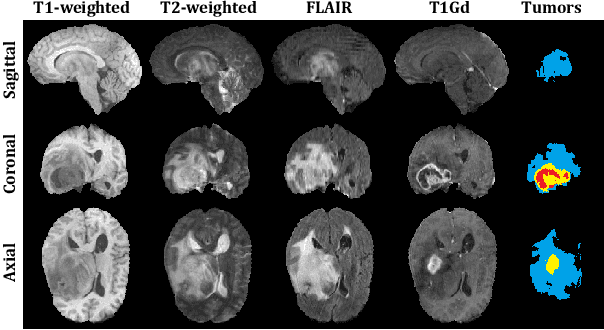

Abstract:Past few years have witnessed the artificial intelligence inspired evolution in various medical fields. The diagnosis and treatment of gliomas -- one of the most commonly seen brain tumors with low survival rate -- rely heavily on the computer assisted segmentation process undertaken on the magnetic resonance imaging (MRI) scans. Although the encoder-decoder shaped deep learning networks have been the de facto standard style for semantic segmentation tasks in medical imaging analysis, enormous effort is still required to be spent on designing the detailed architecture of the down-sampling and up-sampling blocks. In this work, we propose a neural architecture search (NAS) based solution to brain tumor segmentation tasks on multimodal volumetric MRI scans. Three sets of candidate operations are composed respectively for three kinds of basic building blocks in which each operation is assigned with a specific probabilistic parameter to be learned. Through alternately updating the weights of operations and the other parameters in the network, the searching mechanism ends up with two optimal structures for the upward and downward blocks. Moreover, the developed solution also integrates normalization and patching strategies tailored for brain MRI processing. Extensive comparative experiments on the BraTS 2019 dataset demonstrate that the proposed algorithm not only could relieve the pressure of fabricating block architectures but also possesses competitive feasibility and scalability.

Abstract:Past few years have witnessed the prevalence of deep learning in many application scenarios, among which is medical image processing. Diagnosis and treatment of brain tumors require a delicate segmentation of brain tumors as a prerequisite. However, such kind of work conventionally costs cerebral surgeons a lot of precious time. Computer vision techniques could provide surgeons a relief from the tedious marking procedure. In this paper, a 3D U-net based deep learning model has been trained with the help of brain-wise normalization and patching strategies for the brain tumor segmentation task in BraTS 2019 competition. Dice coefficients for enhancing tumor, tumor core, and the whole tumor are 0.737, 0.807 and 0.894 respectively on validation dataset. Furthermore, numerical features extracted from predicted tumor labels have been used for the overall survival days prediction task. The prediction accuracy on validation dataset is 0.448.